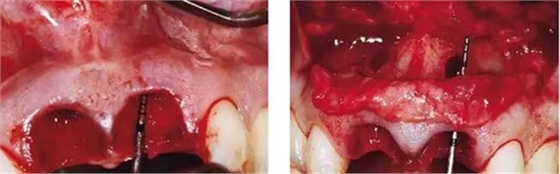

圖1、該病例顯示了厚齦生物型和中弧線形齦乳頭形態(tài)。右上中切牙由于牙根縱裂而需要拔除。由于該患牙伸長,使得軟組織量垂直向增加。牙齦色素沉著是個美學(xué)挑戰(zhàn)。

圖2、翻開全厚瓣可見明顯的牙根縱裂,唇側(cè)骨板2/3受到累及而缺損。

圖3、拔牙后看到更大范圍的骨缺損,并且缺損導(dǎo)致上頜側(cè)切牙根尖牙骨質(zhì)暴露,繼而存在術(shù)后由于軟硬組織退縮而帶來的美學(xué)風(fēng)險。